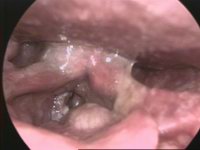

image الإنجليزية

Tumor Laryngis-01.jpg

٢٠٠ × ١٥٠؛ ٦ كيلوبايت

media legend الإنجليزية

Cáncer de laringe en visión endoscópica (الإسبانية)